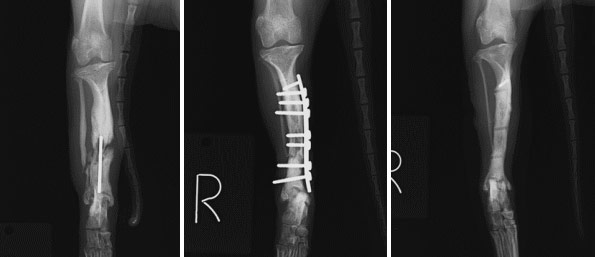

症例1イタリアン・グレイハウンド 5ヵ月齢 5.2kg

橈尺骨骨幹部横骨折 φ2.4mmロッキングプレート固定